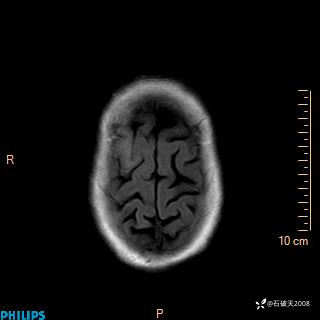

2020.11.14MR

T2